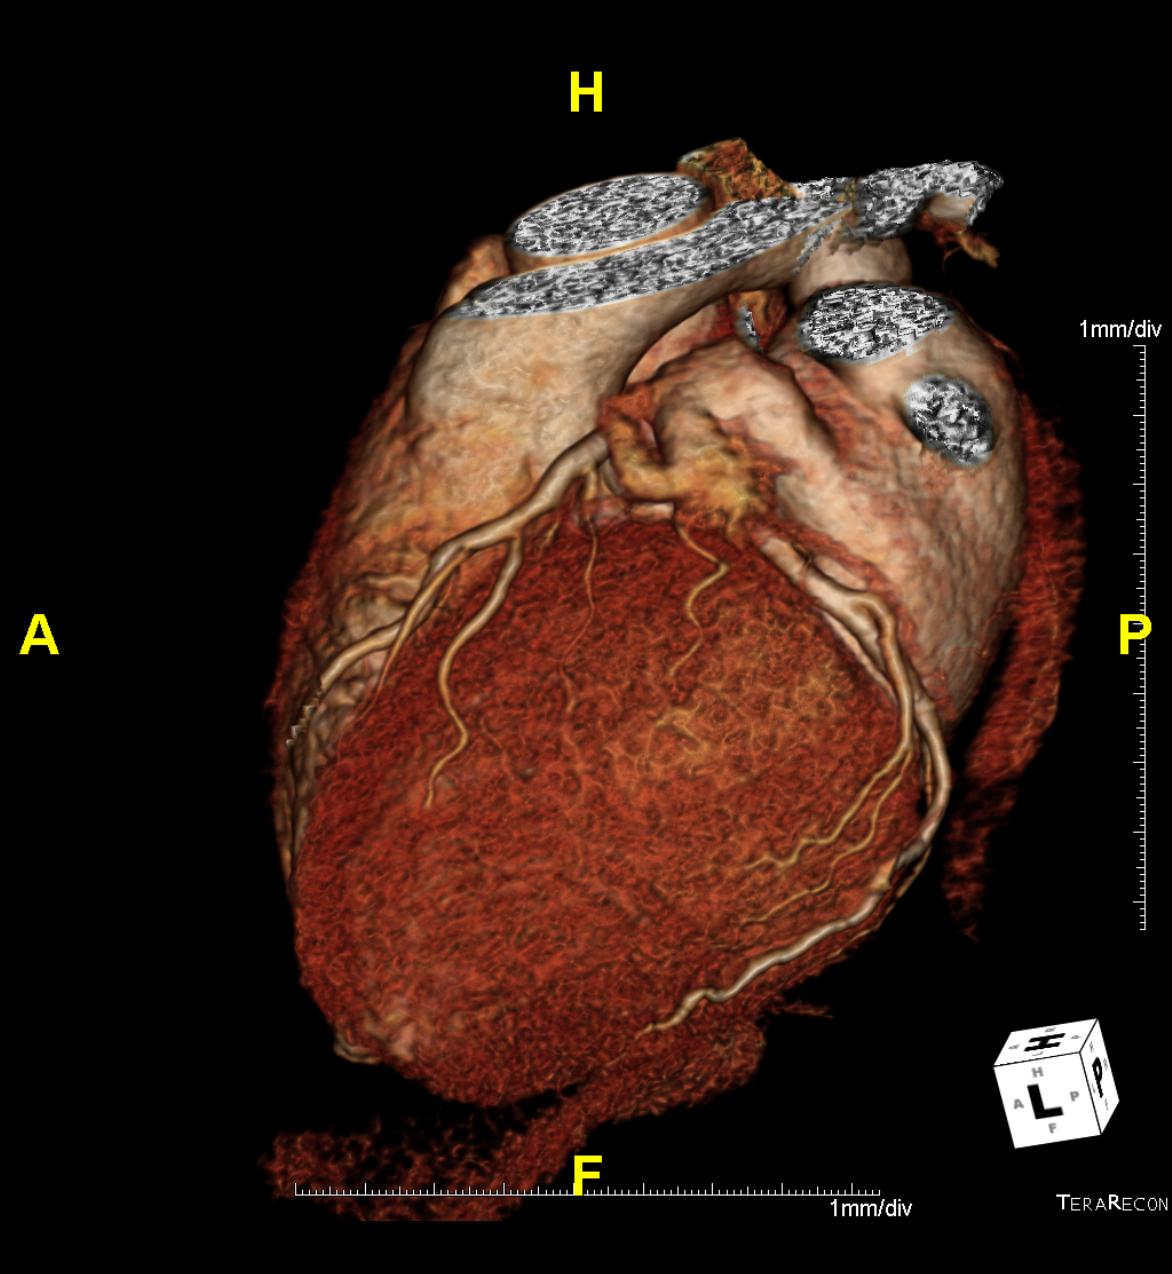

Das Klinikum Ludwigshafen verfügt über einen Kardio-CT der neuesten Generation: Das 128-Zeilen-Gerät ermöglicht eine äußerst präzise Untersuchungsmethode zur Darstellung der Herzkranzgefäße des schlagenden Herzens.

Die koronare Herzerkrankung (KHK) ist eine der häufigsten Erkrankungen in der westlichen Welt. Bei dieser Erkrankung führen Kalkablagerungen an der Gefäßwand (Arteriosklerose) zur Verengung des betroffenen Gefäßes. Diese Engstellen (Stenosen) vermindern die Blutversorgung des Herzmuskels. Kommt es mit dem Fortschreiten der KHK zum Gefäßverschluss, entsteht ein Herzinfarkt.

Die Computertomografie des Herzens (Kardio-CT) ist eine Methode, die frühen Stadien der KHK zu erkennen, bzw. eine KHK mit an Sicherheit grenzender Wahrscheinlichkeit ausschließen zu können.

Prinzipiell ist die Kardio-CT eine Computertomografie (CT), also eine Röntgenuntersuchung, bei der die Röntgenröhre spiralartig um den Patient rotiert. Das Besondere ist die enorme Leistungsfähigkeit der CT, bei der mehrere, sehr dünne Schichten pro Umdrehung gleichzeitig aufgenommen werden.

In Ludwigshafen verwenden wir einen CT der neuesten Generation der Firma Siemens, mit dem wir 128 Schichten pro Umdrehung aufnehmen. Auf diese Weise lässt sich das gesamte Herz mit nur vier bis fünf Umdrehungen erfassen. Für Sie bedeutet das, dass wir Ihre Herzkranzgefäße in der derzeit bestmöglichen Auflösung und mit geringst möglicher Strahlenbelastung darstellen können.

Die eigentliche Untersuchung dauert also nur wenige Sekunden. Wir bitten Sie aber, insgesamt etwa 1,5 Stunden einzuplanen, da die Vorbereitung, das Erstellen des Befundes und die Besprechung des Befundes mit Ihnen mehr Zeit benötigt als die Untersuchung selbst.

Vor der Untersuchung messen wir Ihren Puls. Sollte der Puls schneller als 65 Schläge pro Minute betragen, geben wir Ihnen einen kurz wirksamen Betablocker, um einen Zielpuls von etwa 60 Schlägen pro Minute zu erreichen. Dazu muss Ihnen eine Verweilkanüle gelegt werden, die auch später zur Kontrastmittelinjektion verwendet wird.

Um die Herzkranzgefäße überhaupt sehen zu können, bekommen Sie etwa 70 ml eines Kontrastmittels (Imeron) in eine Armvene injiziert.